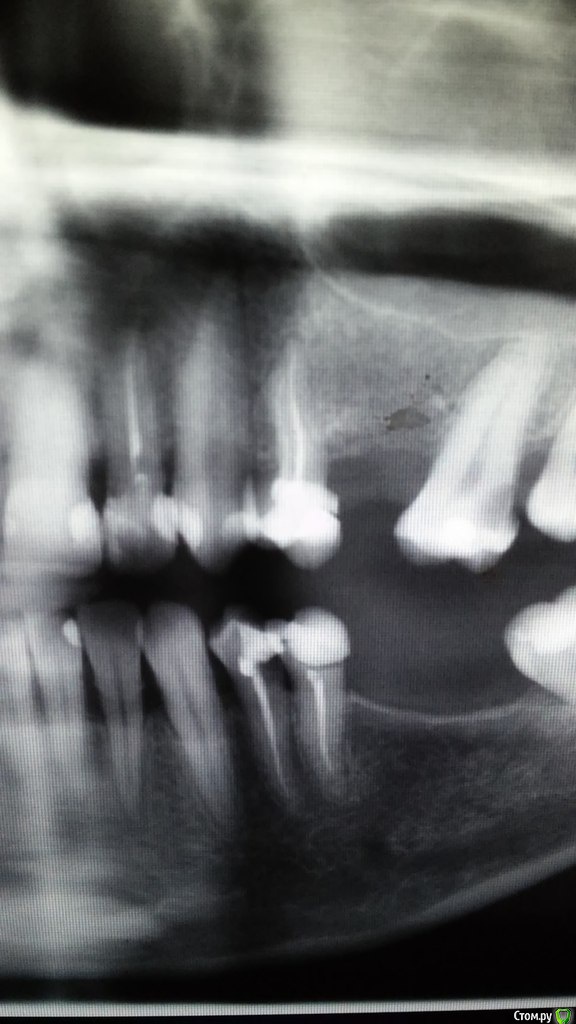

ksanta Опубликовано 9 июля, 2015 Поделиться Опубликовано 9 июля, 2015 При накусывании больно верхнюю 4 и 6 Ссылка на комментарий

shishok Опубликовано 9 июля, 2015 Поделиться Опубликовано 9 июля, 2015 На 6 на задней поверхности-скрытая кариозная полость,на нижнем 4-аналогично.А верхний 4 лечили давно? Ссылка на комментарий

shishok Опубликовано 9 июля, 2015 Поделиться Опубликовано 9 июля, 2015 На 4 верхнем не всё благополучно на верхушке,лучше перелечить каналы+к этому значительная перегрузка зуба. Ссылка на комментарий